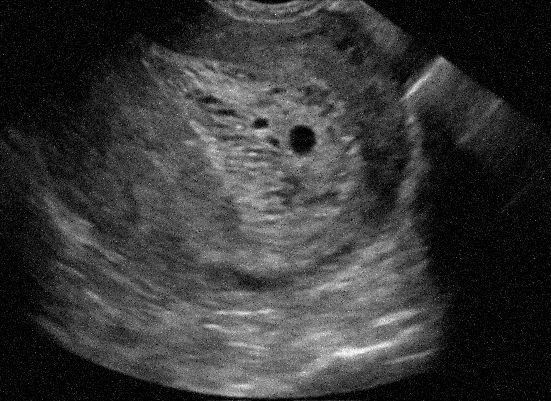

Example 2: restoration of images corrupted by blur and SPN or AWLN. In this example we evaluate the performance of the proposed TV-L1 model on three medical test images lungs (), Fig. 5 (a), ecography (), Fig. 6 (a), and aneurism (), Fig. 7 (a), synthetically corrupted by Gaussian blur of parameters band=5 and sigma=1 and by two types of impulsive noise, namely SPN and AWLN.

| (a) original | (b) TV-L1 (ISNR = 22.13) | (c) zoom of (b) |

![]() |

| (d) corrupted | (e) TVp-L1 (ISNR = 23.15) | (f) zoom of (e) |

| (g) -map () | (h) TV-L1 (ISNR = 25.46) | (i) zoom of (h) |

| (l) -map () | (m) TV-L1 (ISNR = 28.01) | (n) zoom of (m) |

First, for what concerns corruptions by SPN, in Figs. 5, 6, 7 we report for the three considered test images the original and corrupted image together with the estimated -maps in the first column (with the size of the neighborhoods used for the -maps estimation reported in the captions), the restoration results, obtained by the four compared methods, in the second column (with the achieved ISNR values in the captions) and a zoomed detail of the restored images - green- bordered in Figs. 5 (a), 6 (a), 7 (a) - in the last column.

The reported ISNR values as well as the visual inspection of the restored images and of the zoomed details strongly indicate how the proposed space-variant regularizer allows for higher quality restorations. In particular, it is worth remarking how, with respect to the space-variant TV model, the additional degrees of freedom represented by the scale parameters used in our proposal, yield a sufficient additional flexibility for avoiding unwanted spurious effects - see, e.g., spikes in Figs. 5 (i), 6 (i), 7 (i).